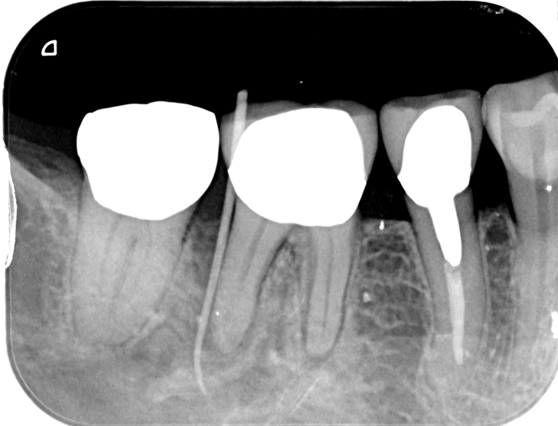

根管治療 症例2

経過観察2年で症状なく良好な治癒経過を確認

根管治療することにより治療の影響で一時的に痛みが強くなることがあります。